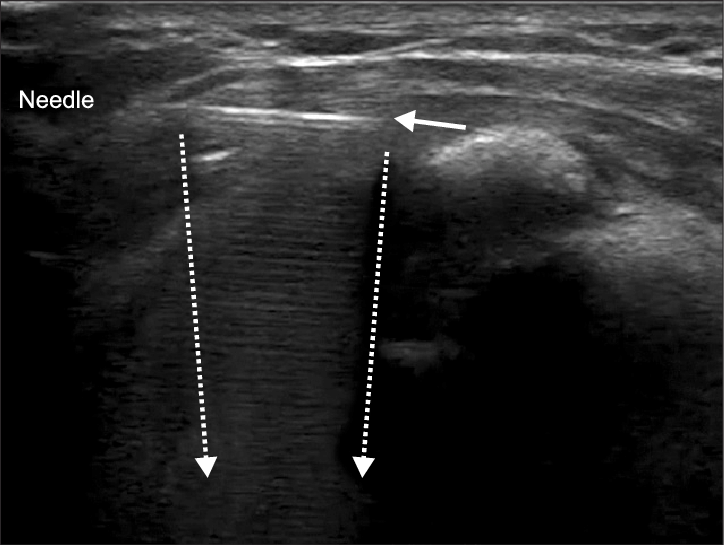

Cola de cometa

La cola de cometa es un artefacto de reverberación: aparece como una estela de ecos brillantes que se repite hacia la profundidad a partir de un punto muy reflectante.

La imagen se vería así:

Este artefacto está asociado a pequeñas calcificaciones, interfaces muy reflectantes o material extraño como una aguja, por ejemplo, al realizar una técnica invasiva.

Para no confundirte, fíjate en su comportamiento: suele mantenerse anclada al reflector que la genera y cambia bastante si modificas el ángulo o el apoyo de la sonda.

Ante la duda, haz siempre la exploración en dos planos y baja un poco la ganancia si la imagen se ve demasiado brillante. La reverberación se intensifica cuando la ganancia es alta.